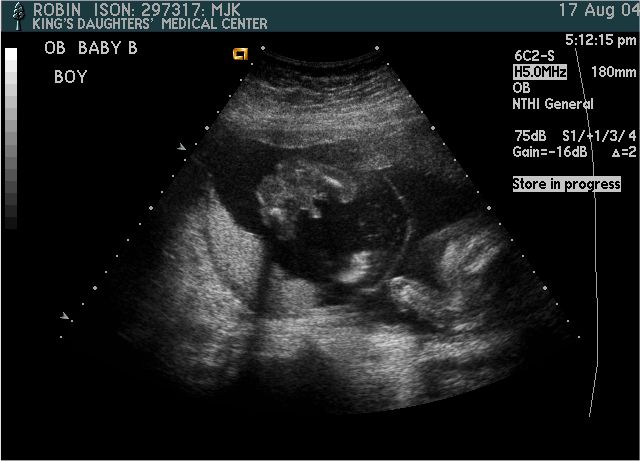

Baby B

Pictures from Ultrasound at 20 weeks.